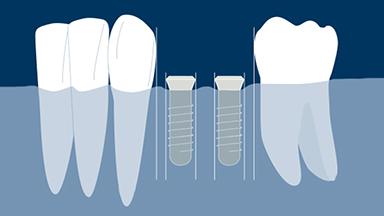

Surgical Assessment of the Implant Site

The focus of this module is surgical assessment of the edentulous site after the teeth have been extracted and the ridge has healed.

- describe the factors required to assess the soft tissues at the implant site

- describe the factors required to assess the bone at the implant site

- describe the relationship between the planned prosthesis and the implant site

- determine the need for bone augmentation at the implant site